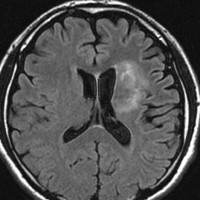

放射線治療後9週目

フレア画像です。たった2週間で脳浮腫が高度の脳浮腫となっています。失語症と右片麻痺と認知機能低下が生じました。ステロイド剤とグリセリンの点滴を行いました。